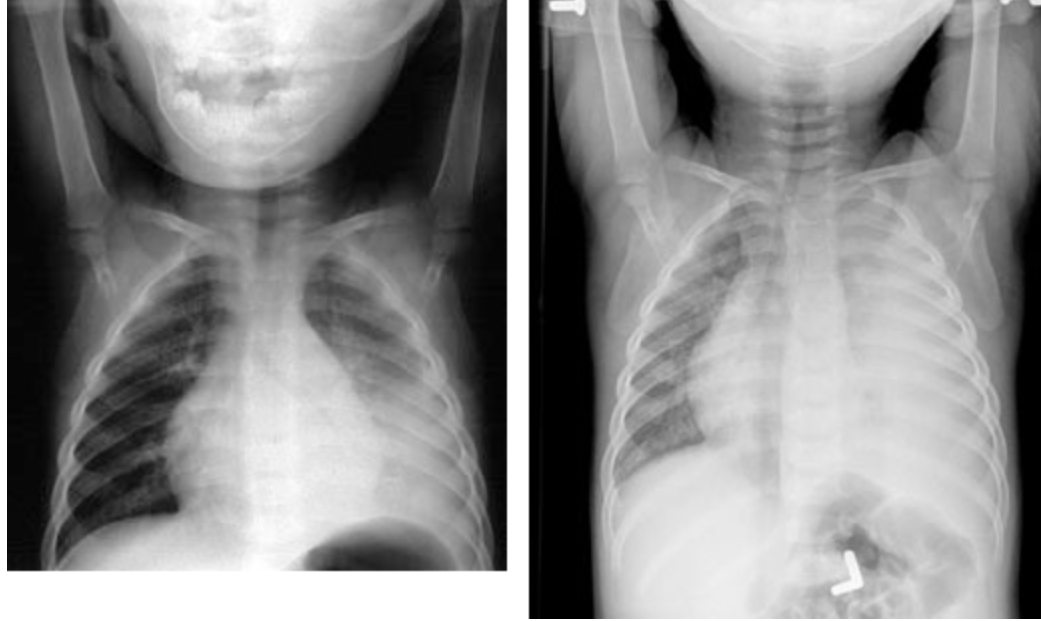

A full-term 8-hour-old male newborn regurgitates his first feeding. He drools constantly and has not urinated or had a bowel movement. His pulse is 136/min, and respirations are 68/min. There are no intercostal retractions. The remainder of the examination shows no abnormalities. Which of the following is the most appropriate initial diagnostic procedure?